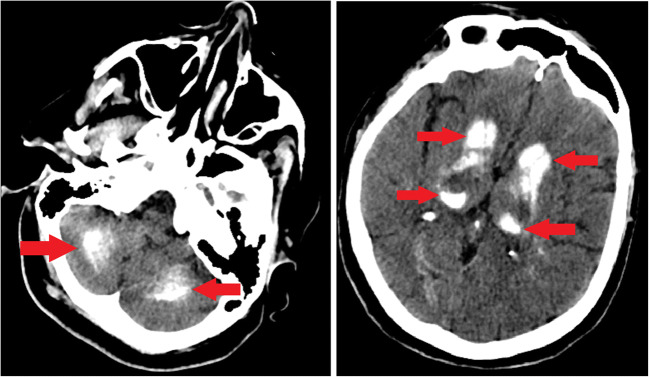

On the 2nd day in the ICU, the patient had a tonic-clonic convulsion starting from the left arm and spreading to the whole body. She was successfully treated with 2 mg of intravenous midazolam. We observed that calcium level was 5.4 mg/dL, albumin level was 31.8 g/L, and phosphorus level was 7.8 mg/dL in the laboratory tests. Calcium replacement was started and 0.5 mcg of calcitriol was added to the treatment twice a day after consultation with endocrinology department. Calcium level increased to 7.5 mg/dL after replacement therapy. Levetiracetam was added to the treatment as anticonvulsant and a cranial CT imaging was ordered for identifying the underlying etiology of the seizure. The cranial CT scan showed bilateral calcifications at the corona radiata, nucleus dentatus, basal ganglia, and cerebellum (Fig. 1). Based on these findings, the patient was diagnosed as Fahr’s syndrome. A blood metabolic panel test was ordered which showed that parathormone (PTH) level was 2.8 ng/L and 25-hydroxy-vitamin D level was 5.36 mcg/L. It was considered that the underlying etiology of Fahr’s syndrome was hypoparathyroidism.

Fig. 1.

Calcifications at the levels of cerebellum and basal ganglia

Our patient was asymptomatic without any movement disorder or neuropsychiatric symptoms and Fahr’s disease presented with generalized tonic-clonic seizure in the ICU. The seizures were seen after the patient was admitted to the ICU and a computerized tomography cranial imaging was ordered to investigate the etiology of the seizures. Cranial CT scan showed bilateral calcifications at the corona radiata, nucleus dentatus, basal ganglia, and cerebellum. The CT scan findings were interpreted as in favor of Fahr’s syndrome. A further blood chemistry metabolic panel test showed hypocalcemia and hypoparathyroidism.